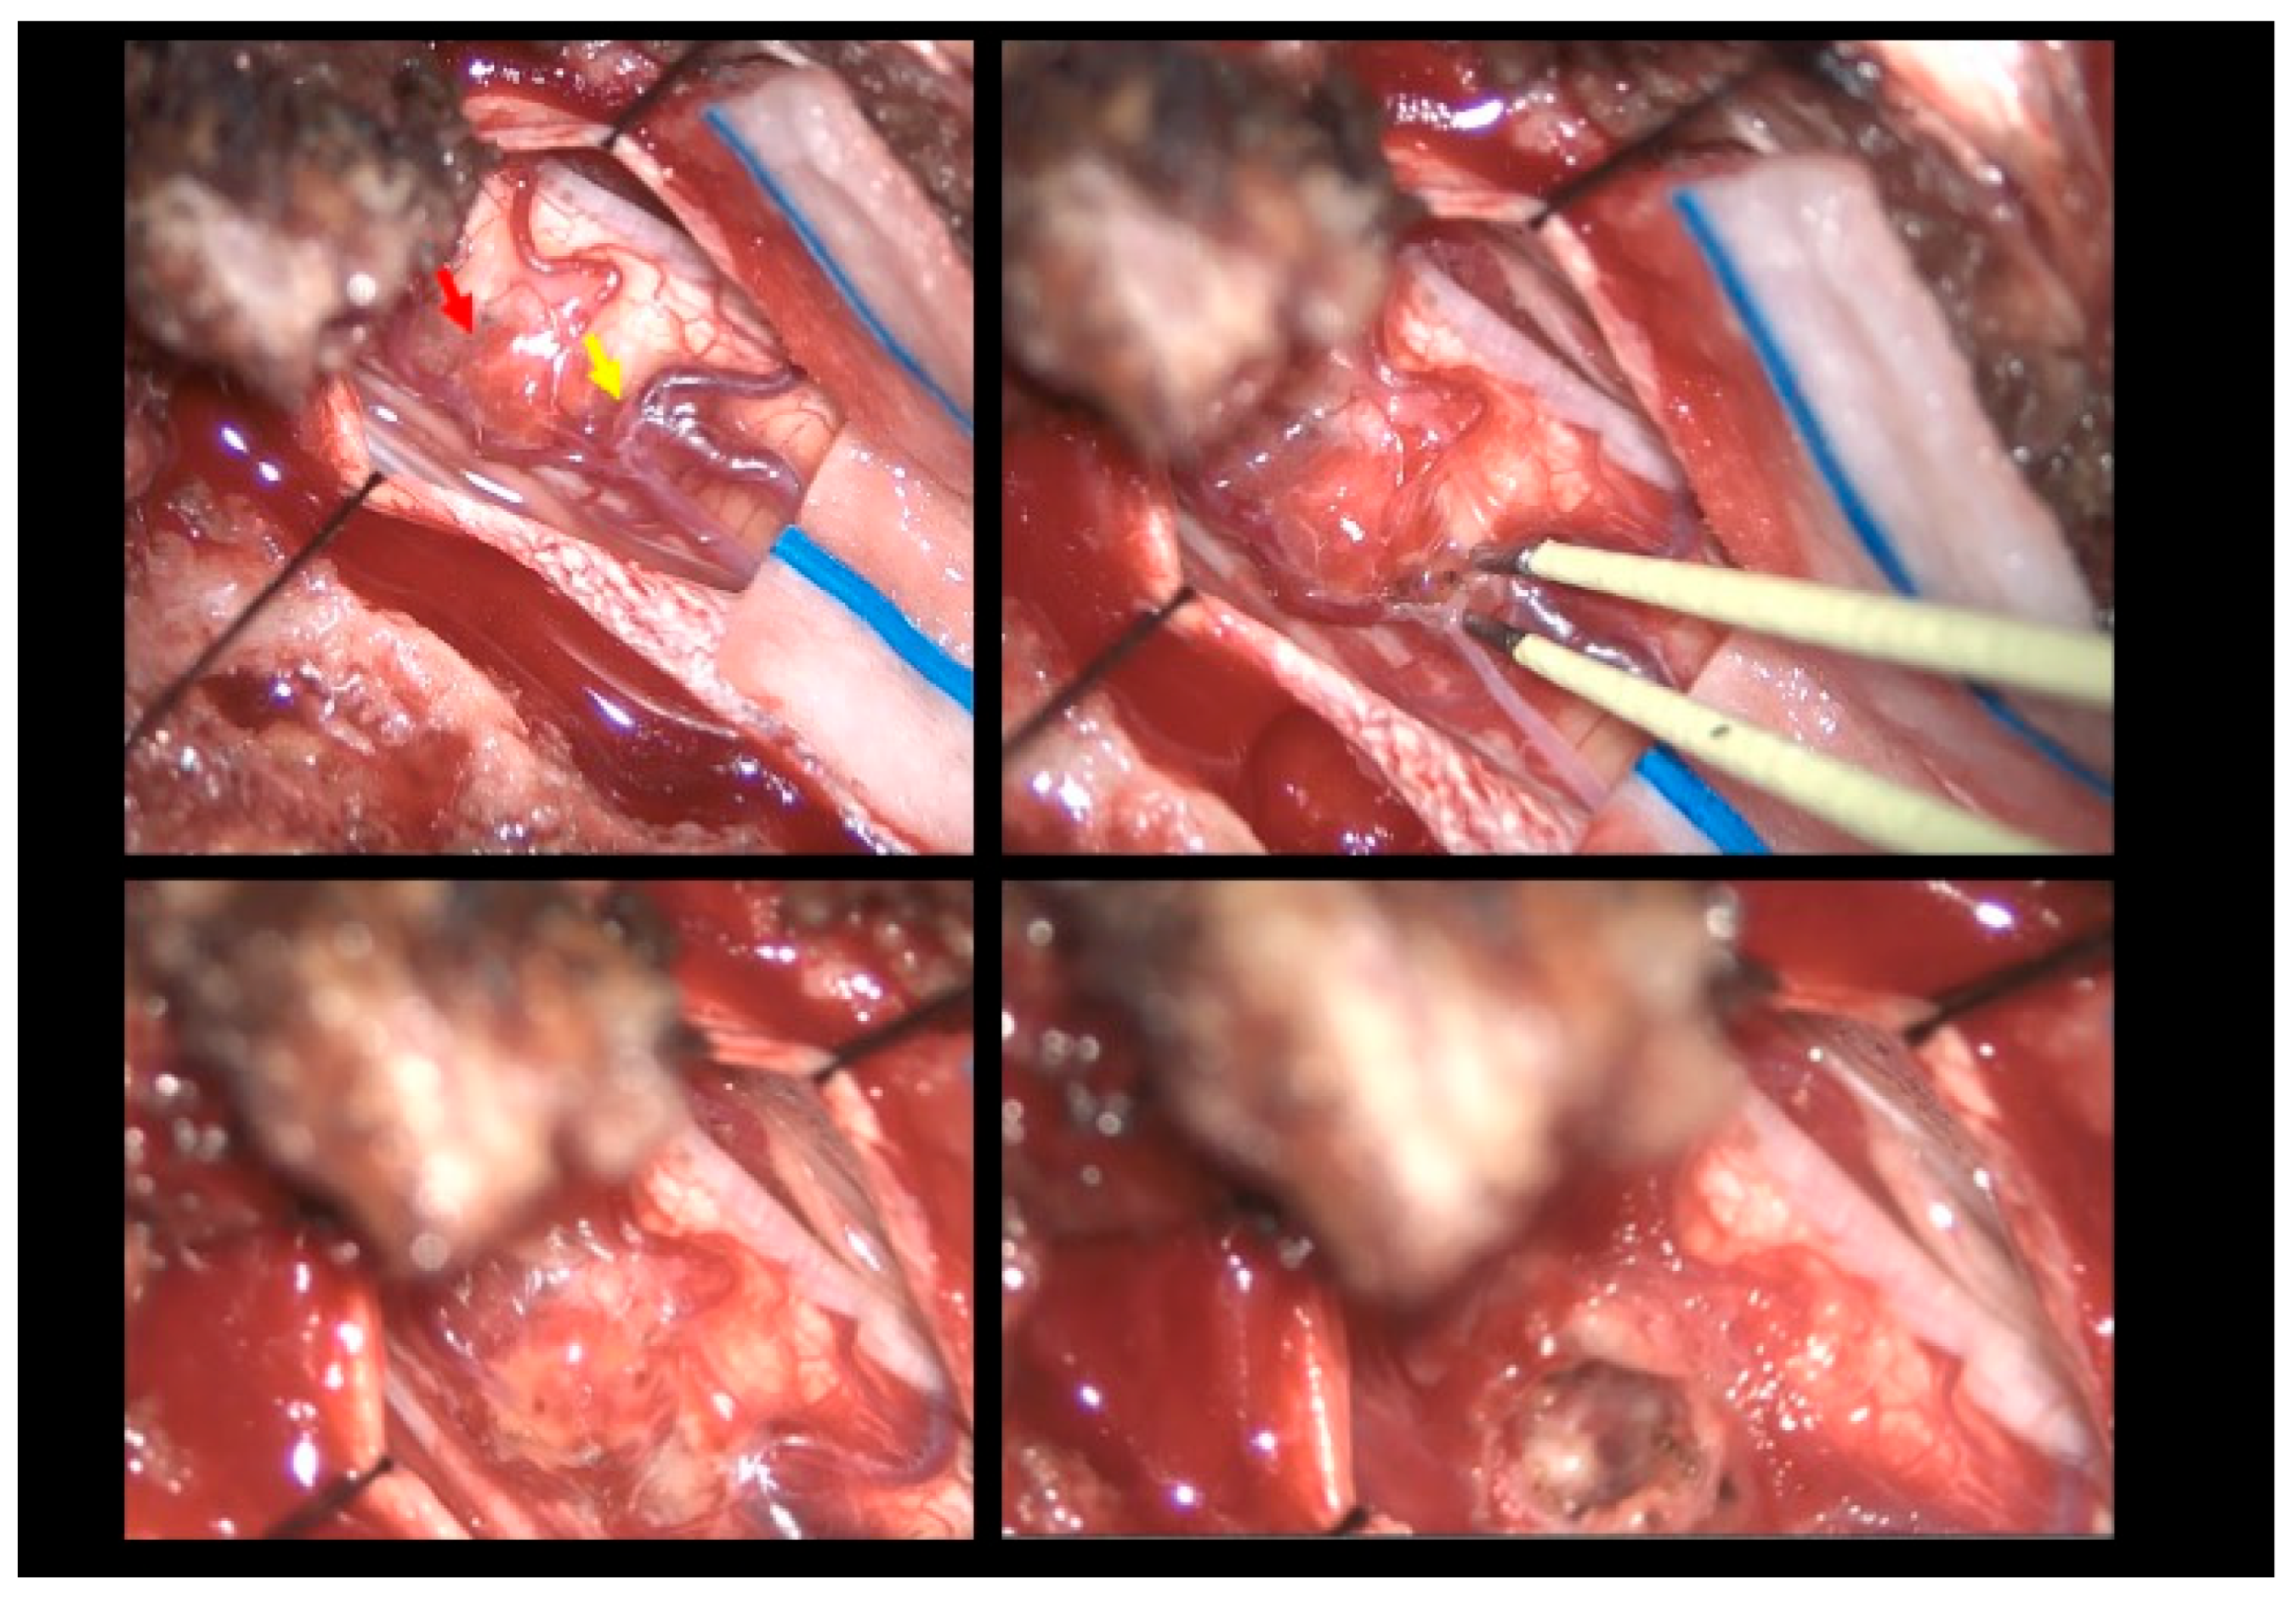

Figure 3.

Intraoperative findings. Upper left: Visualization of the hemangioma (red arrow) associated with the vascular malformation resembling a dural arteriovenous fistula (yellow arrow). Upper right: Sealing of the fistula using bipolar cautery. Bottom left: Macroscopic color change following fistula closure. Bottom right: Macroscopic appearance following hemangioma removal.